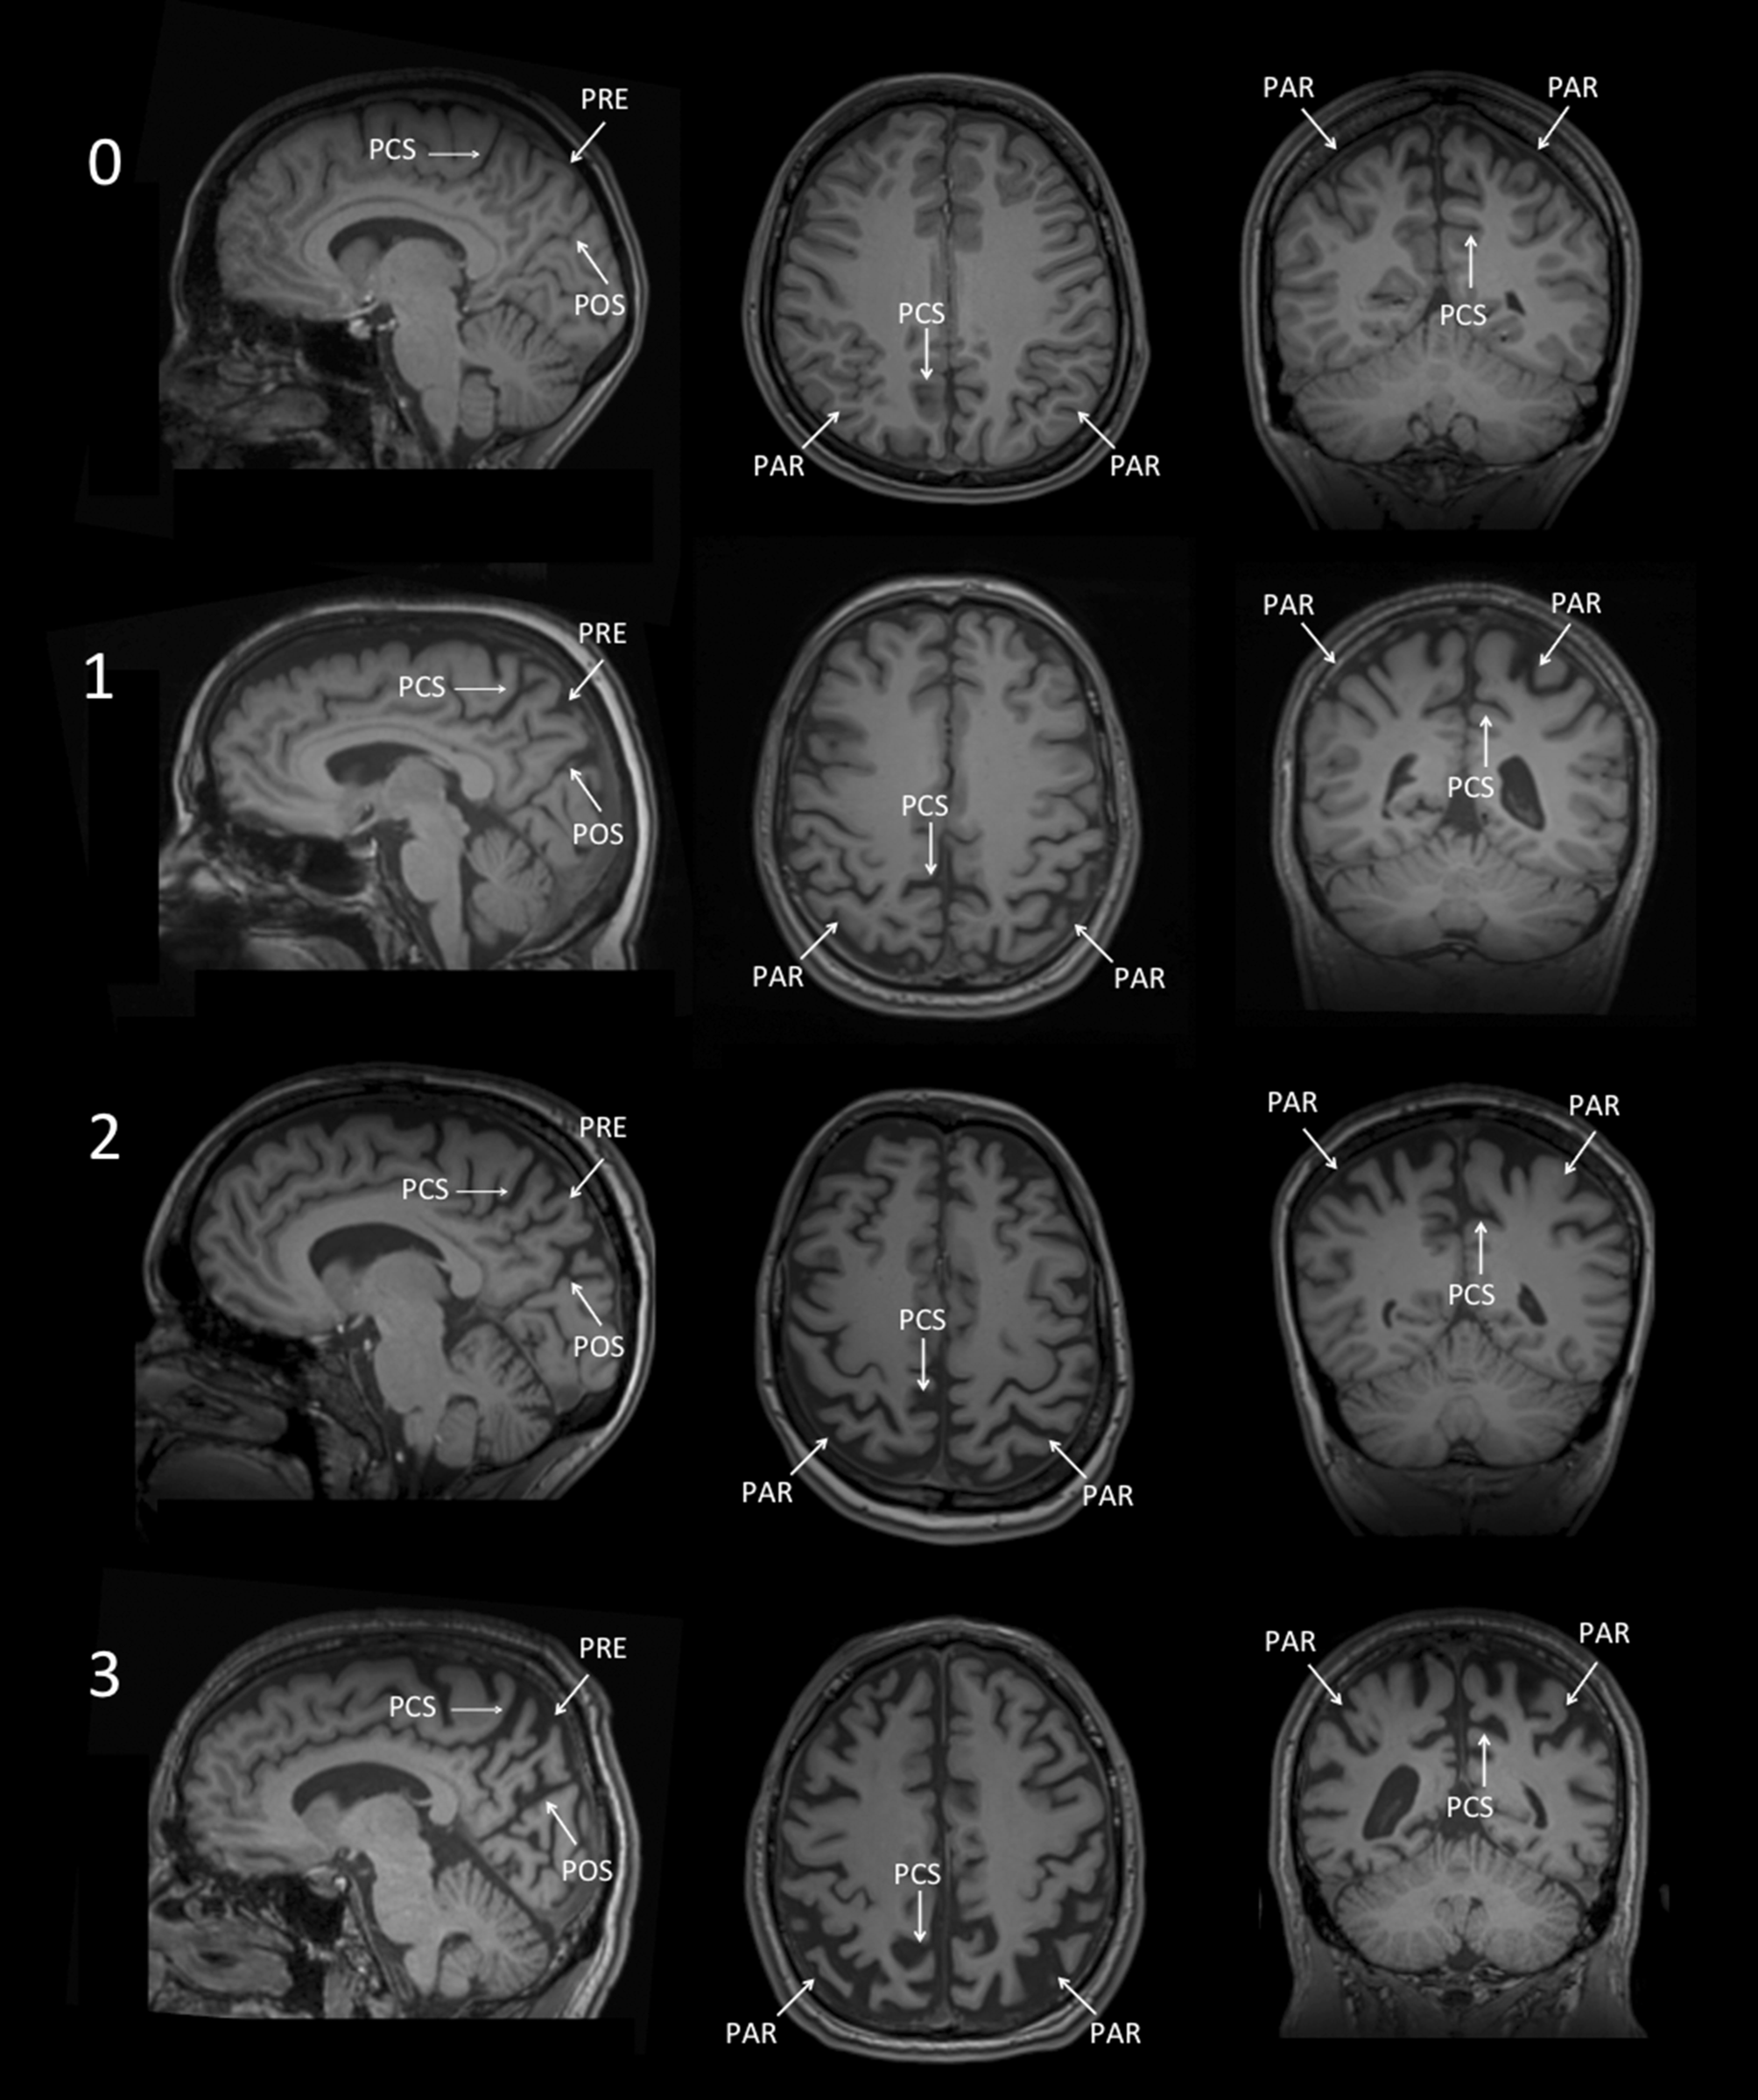

Posterior/parietal atrophy

The posterior/parietal atrophy score (Koedam score) has been designed to visually evaluate the posterior cingulate, precuneus and superior parietal regions on a four-step scale (illustrated in Fig. 3; [2]). To generate the score, the MR images of the brain have to be viewed in axial, coronal and sagittal planes assessing the following structures:

• sagittal plane:

precuneus gyrus (PRE)

posterior cingulate sulcus (PCS)

parieto-occipital sulcus (POS)

• axial plane

parietal gyrus (PAR)

• coronal plane

A posterior/parietal atrophy score of 0 represents a normal width of the above mentioned sulci and no atrophy of the precuneus, while score of 1, 2 or 3 is characterized by mild, moderate or severe widening of the sulci and precuneus atrophy, respectively.

Fig. 3

Posterior/parietal atrophy score